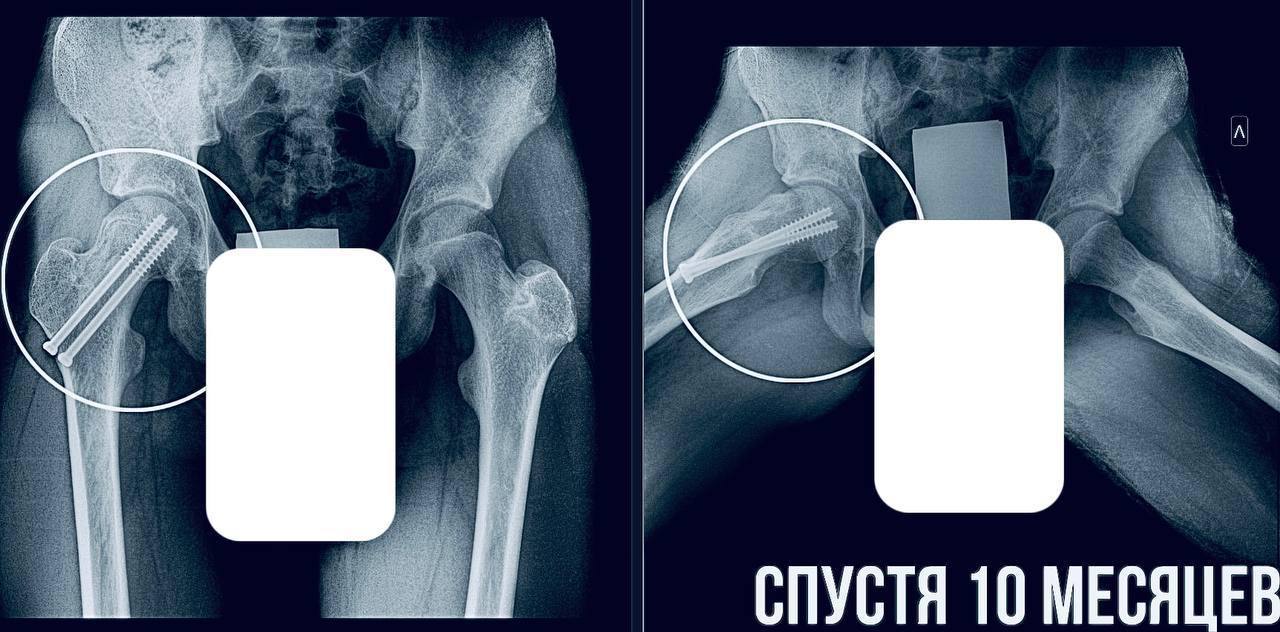

Врачи срочно провели фиксацию сустава, чтобы остановить смещение и предотвратить ранний артроз. Подросток уже идет на поправку и скоро начнёт реабилитацию.